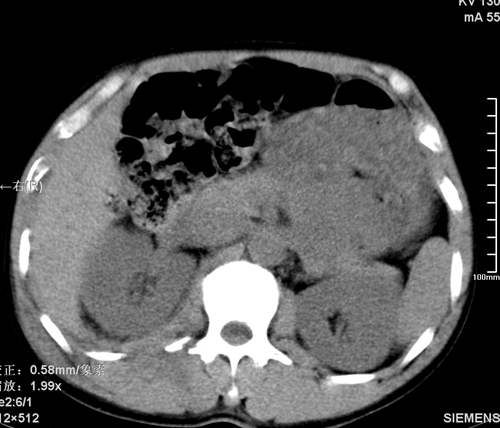

以下是引用tao772在2008-3-28 12:29:00的发言:[br]右侧腹膜后积血,右侧腰大肌挫伤,右侧部分横突骨折. 肾脏最好报一下挫伤,必要时增强。